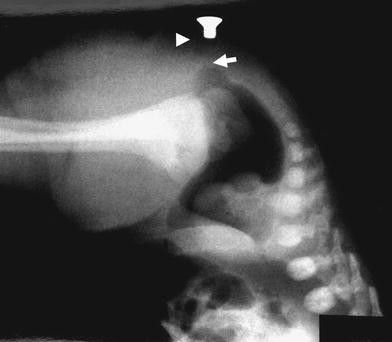

A recto-vestibular fistula is the most common anorectal malformation seen in female patients . The condition is characterized by a connection between the rectum and the vaginal vestibule, at the lower aspect of the vaginal opening . The condition can cause feces and gas to exit the vaginal vestibule .